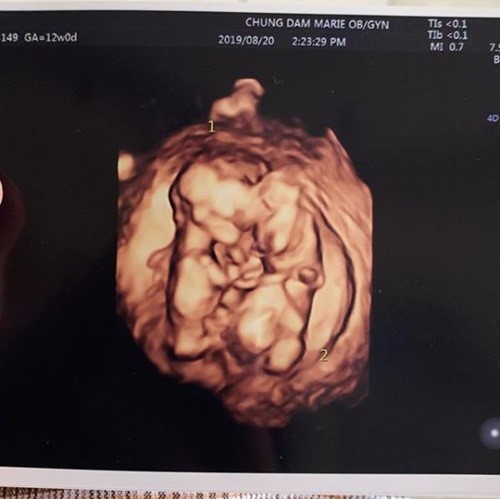

이어 쌍둥이 초음파 사진과 함께 "둥이들은 이렇게 서로 꼭 붙어 잘 크고 있다. 다시 한 번 축하해주셔서 감사드린다"고 덧붙였다.

둥이들은 이렇게 서로 꼭 붙어 잘 크고있답니다. 다시한번 축하해주셔서 감사드려요.